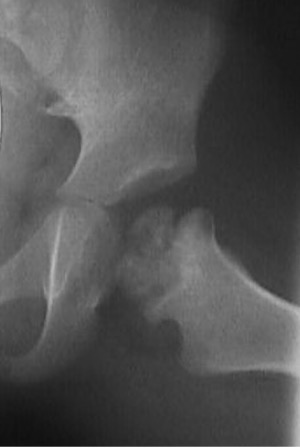

AP X-ray

Timing

AP after 6 months of age when the superior femoral epiphysis becomes ossified

Create 4 quadrants on xray

- Hilgenreiner's Line - horizontal through triradiate cartilages

- Perkin's Line - vertical through lateral edge of bony acetabulum

- superior femoral epiphysis (SFE) should be in inner and lower quadrant

Dislocated hip with smaller superior femoral epiphysis (SFE) and location in the upper outer quadrant

Findings

| Superior femoral epiphysis | Disrupted Shenton's line | Increased acetabular index | Increased head to teardrop distance |

|---|---|---|---|

|

Smaller

In upper/ outer quadrant |

Line along inferior neck

Line inferior border superior ramus |

Angle between Hilgenreiner's line and acetabular line |

Lateral tear drop to medial ossification center |

Normal < 30° DDH > 35° |